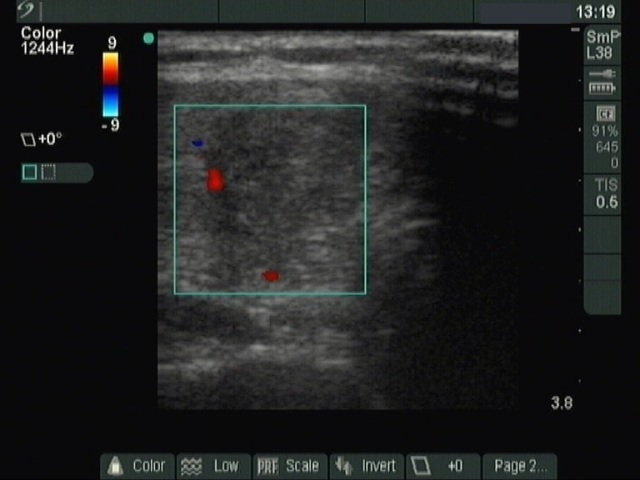

Ultrasonography: a moderately hypoechogenic nodule in the right lobe.